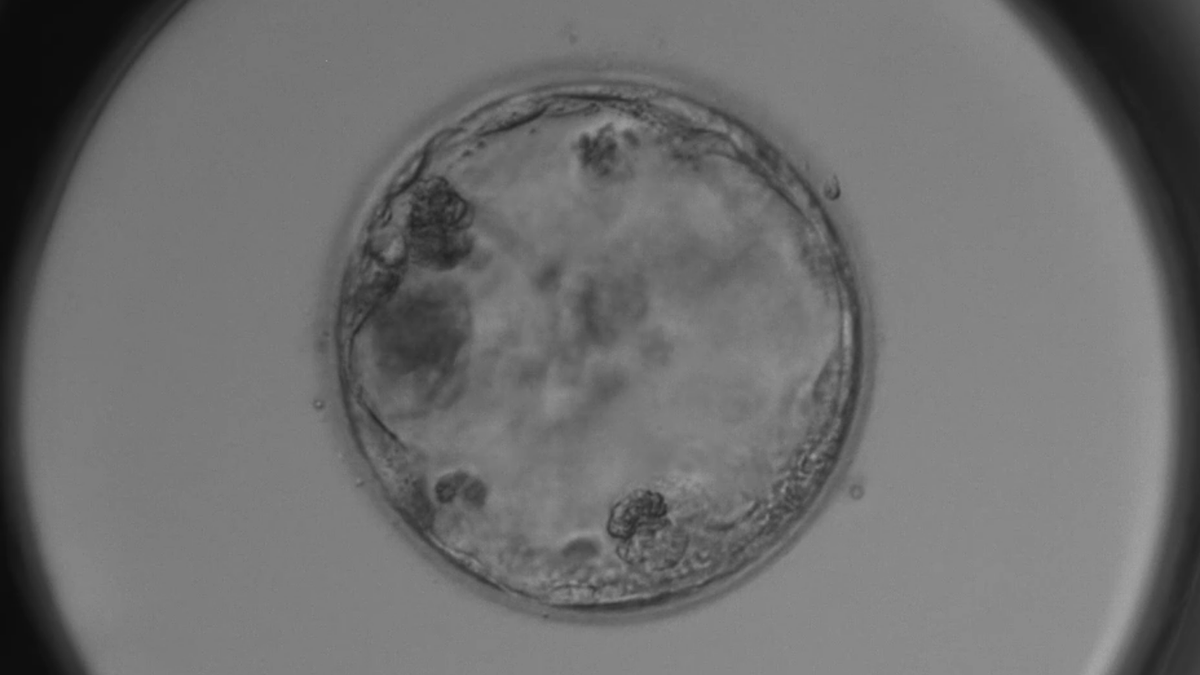

A 4CC graded embryo

Blastocyst is the stage of embryo development that occurs about five days after fertilisation, when the embryo is ready for implantation. Poor quality blastocyst stage embryos are normally given a CC grade, as per the Gardener Grading Score. And as long as they are growing and expanding and not degenerating, they should be considered.